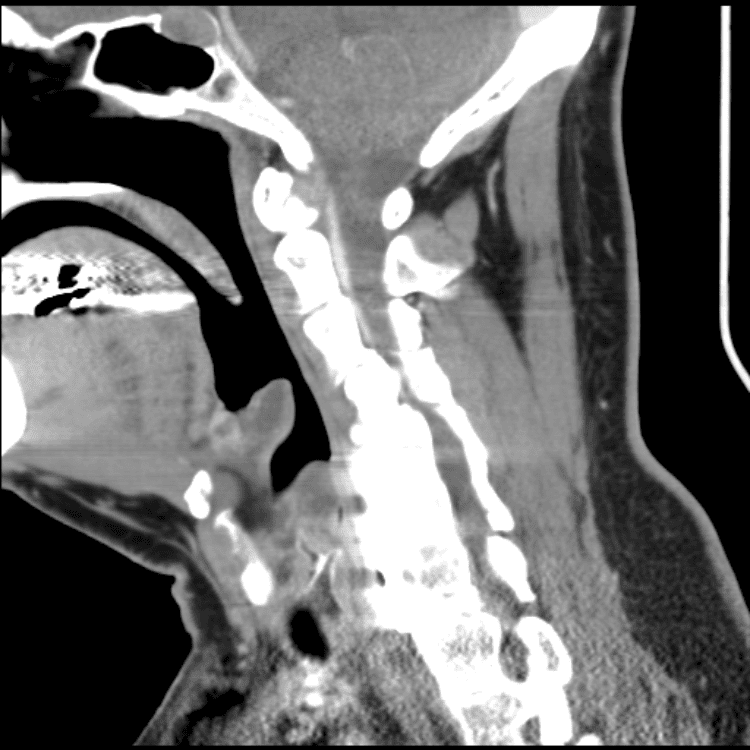

Head and Neck

Practice

Simulates call by including subtle or difficult cases and some normals.

27 cases